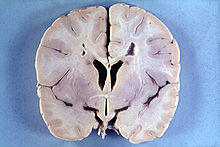

| An MRI of a patient with benign familial macrocephaly (male with head circumference > 60cm) | |

Macrocephaly is a condition in which the human head is abnormally large; this includes the scalp, the cranial bone, and the contents of the cranium. It may be pathological or benign, even a familial genetic characteristic. People diagnosed with macrocephaly will have further testing done to determine whether the syndrome is accompanied by any other disorders. Those with benign or familial macrocephaly are considered to have megalencephaly, another form of macrocephaly that will not result in the development of neurological disorders in the patient.

Many people with abnormally large heads or large skulls are healthy, but macrocephaly may be pathological. Pathologic macrocephaly may be due to megalencephaly (enlarged brain), hydrocephalus (abnormally increased cerebrospinal fluid), cranial hyperostosis (bone overgrowth), and other conditions. Pathologic macrocephaly is called "syndromic", when it is associated with any other noteworthy condition, and "nonsyndromic" otherwise. Pathologic macrocephaly may be caused by congenital anatomic abnormalities, genetic conditions, or by environmental events.[1]